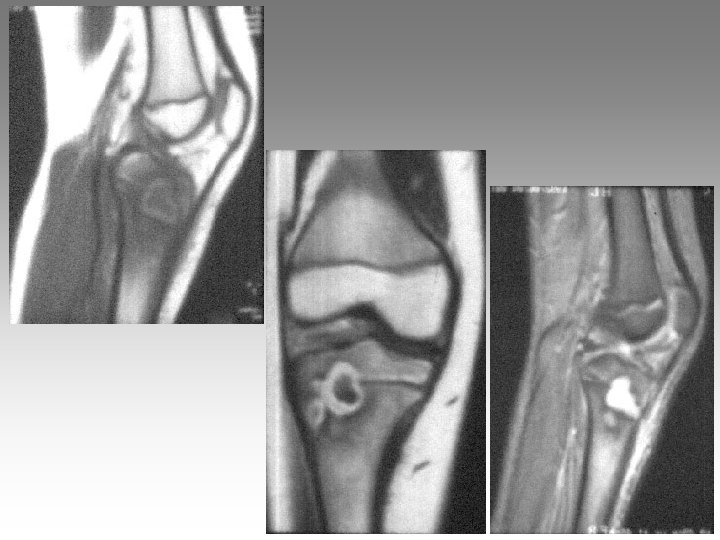

Hanche, T. , fract. fatigue Tendinites bursites, radic. Genou douloureux non traumatique Sémiologie Ponction +++ mécanique inflammatoire Rx inflammation Rx N Rx a. N < 40 ans interligne pincé Arthrose FT - FP contexte +++ > 40 ans Biologie, BS, Rx, IRM, écho interligne normal IRM AND, FF Paget, HOV ONA, OAN OAPH Ostéochond. infection IRM Arthroscopie Scinti. Os. LC Ménisque Coagul. PR, RP, Still, LED, SA…. Goutte, CCA AND ONA Ostéochondrite Pyogène, BK, Gono. , autres Hydarthrose X? Ostéochondromatose Synonite VN, T. , coag.

Genou douloureux non traumatique Sémiologie Ponction +++ mécanique inflammatoire Rx inflammation Rx N Rx a. N < 40 ans interligne pincé Arthrose FT - FP contexte +++ > 40 ans Biologie, BS, Rx, IRM, écho interligne normal IRM AND, FF Paget, HOV ONA, OAN OAPH Ostéochond. infection IRM Arthroscopie Scinti. Os. LC Ménisque Coagul. PR, RP, Still, LED, SA…. Goutte, CCA AND ONA Ostéochondrite Pyogène, BK, Gono. , autres Hydarthrose X? Ostéochondromatose Synonite VN, T. , coag.

Genou douloureux non traumatique Sémiologie Ponction +++ mécanique inflammatoire Rx inflammation Rx N Rx a. N < 40 ans interligne pincé Arthrose FT - FP contexte +++ > 40 ans interligne normal IRM AND, FF Paget, HOV ONA, OAN OAPH infection Biologie, BS, Rx, IRM, écho IRM Arthroscopie Scinti. Os. LC Ménisque Coagul. PR, RP, Still, LED, SA…. Goutte, CCA AND ONA Banal, BK, Gono. , autres Hydarthrose X? Ostéochondromatose Synonite VN, T. osseuse